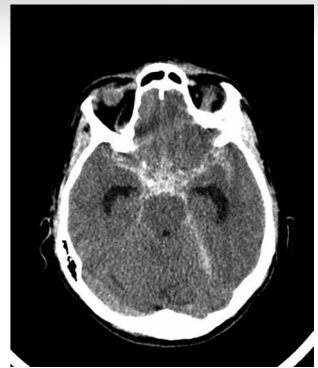

Assinale a alternativa correta em relação a imagem a seguir:

(Arquivo pessoal; imagem usada com autorização)